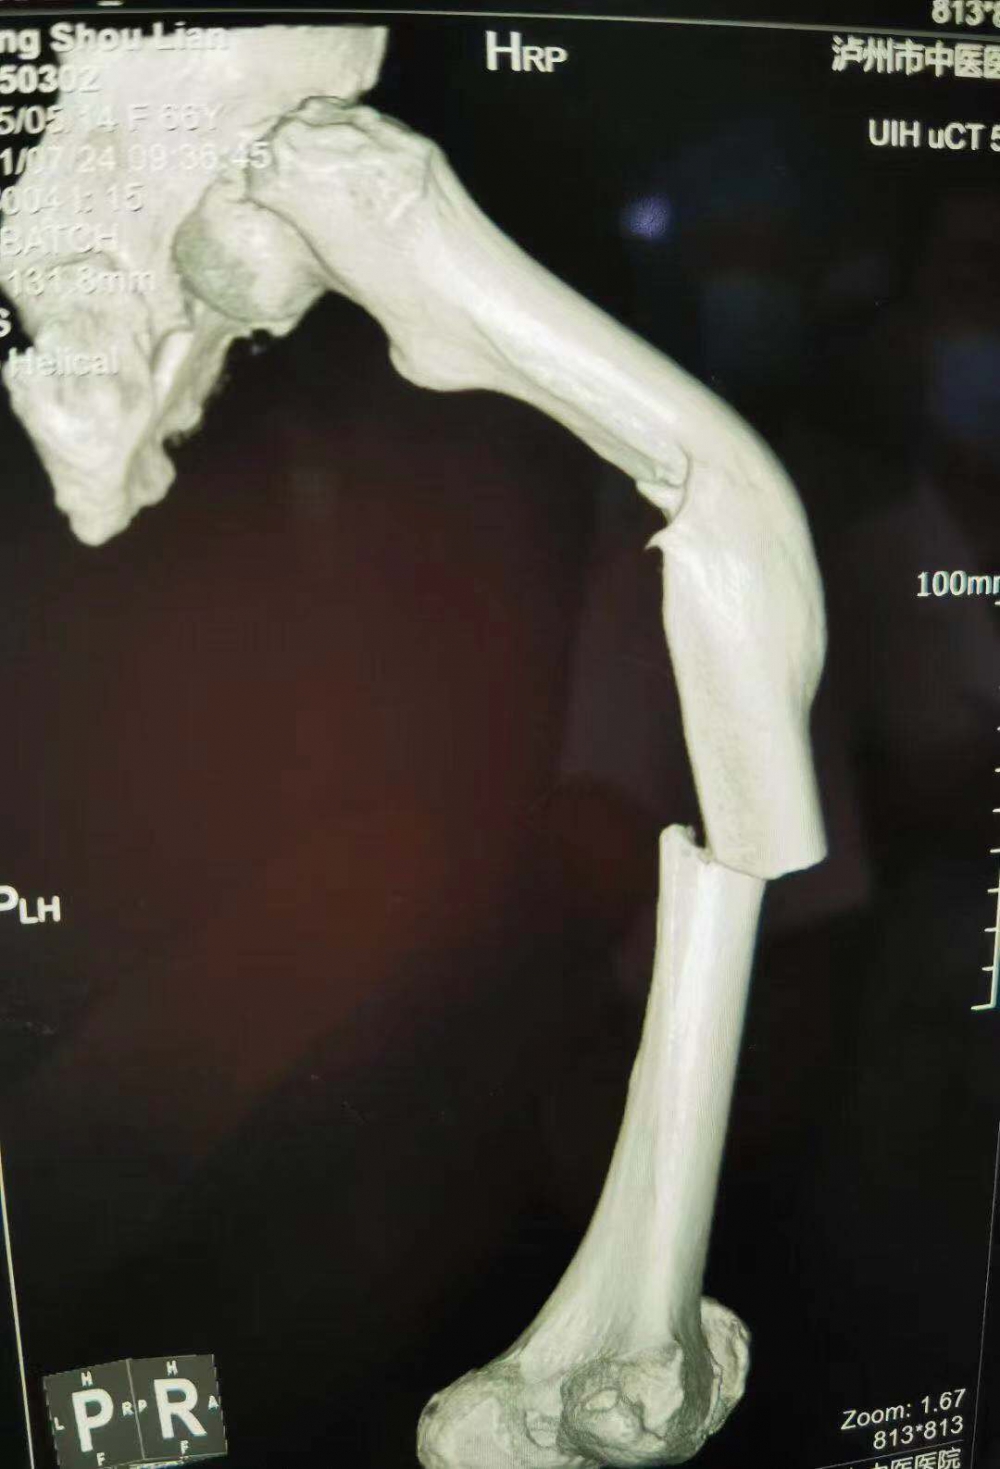

(股骨中段斷裂,上端有明顯畸形)

當(dāng)她的X光片出來(lái)時(shí),收治的醫(yī)生都被她的傷情嚇了一跳。原來(lái)此次她骨折的上端還有一處骨傷畸形愈合。這是什么情況呢?

原來(lái)張守蓮在三年前還摔傷過(guò)一次,當(dāng)時(shí)在一家醫(yī)院進(jìn)行了手法復(fù)位,但因操作不當(dāng),沒(méi)能復(fù)位成功,留下了后遺癥。三年來(lái)她都是以拄拐行走。

據(jù)瀘州市中醫(yī)院骨傷一科主任汪永泉介紹張女士的病情較為復(fù)雜,三年的時(shí)間導(dǎo)致神經(jīng)組織、血管等都已經(jīng)適應(yīng)畸形以后的狀態(tài)。